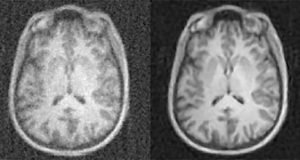

New artificial intelligence technique dramatically improves the quality of medical imaging